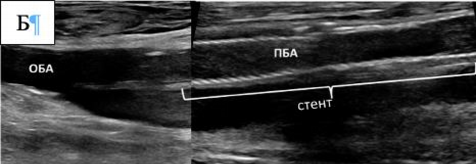

Рекомендуется проводить пункцию под ультразвуковым контролем с целью точного прокола передней стенки артерии и минимизации риска повреждения задней стенки [185, 186].

Комментарий: Анализ пяти РКИ показал, что пункция артерии под УЗ-контролем снижает частоту осложнений по сравнению с пункцией по анатомическим ориентирам [180]. Использование УЗИ уменьшало число попыток пункции (ОШ 0,24), риск прокола вены (ОШ 0,18) и кровотечений (ОШ 0,41). Сравнительных данных об эффективности антеградного и ретроградного доступа при тромболизисе нет. Антеградный доступ через ОБА упрощает реканализацию тромбозов дистальных артерий, а через артерии верхней конечности – прохождение через тромбированную бифуркацию аорты. Ретроградный контралатеральный доступ через ОБА наиболее распространён, обеспечивает стабильное положение катетера и снижает риск смещения и кровотечения [181]. Этот доступ также позволяет избежать необходимости сдавления ОБА ишемизированной нижней конечности при гемостазе, после удаления набора для чрескожного сосудистого доступа (интродьюсер) из места пункции.